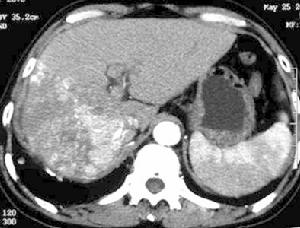

1.微粒栓塞治療巨塊型肝癌伴雙肺多發轉移

2.微粒栓塞治療巨塊型肝癌伴門靜脈主幹及左右支癌栓